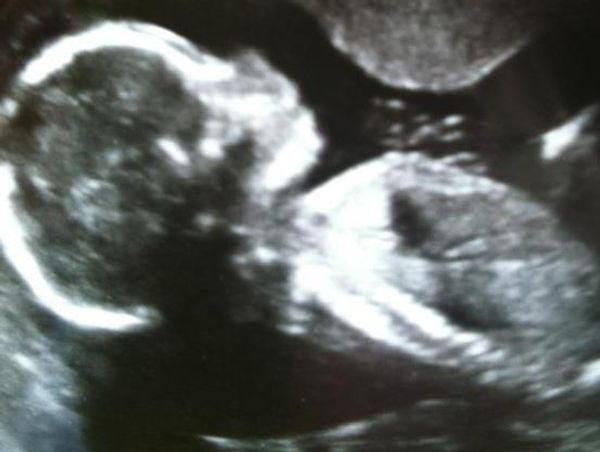

The definition of matrescence is simply the process of becoming a mother. It's the social, psychological, emotional and physical affects a woman goes through to become a mother.

The project explores matrescence through archive images of mothers when they were just girls. Before they were given the responsibility of new life. There's metaphorical imagery, to translate the process of matrescence as its not often something to be seen, but is instead quietly felt. There's also intimate portraits, of mothers and their children, taken by both myself and the mothers and children themselves. This project was a collaboration with mothers for mothers.